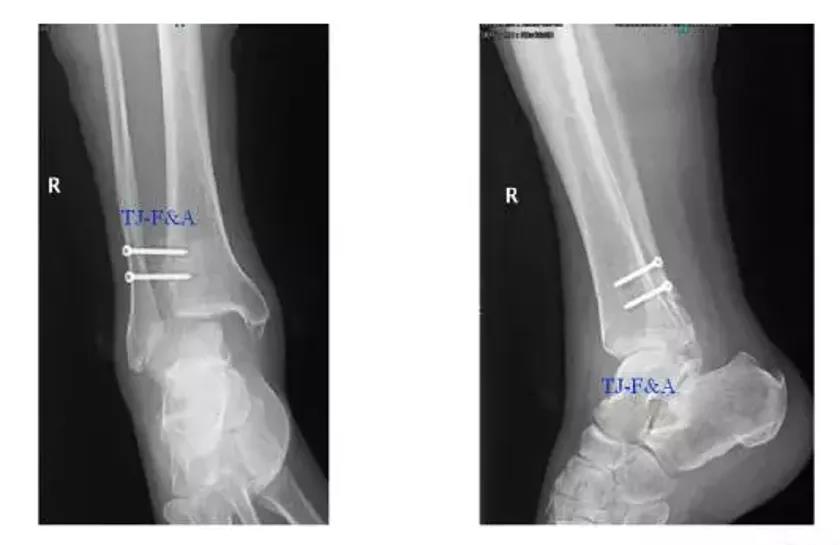

术前DR